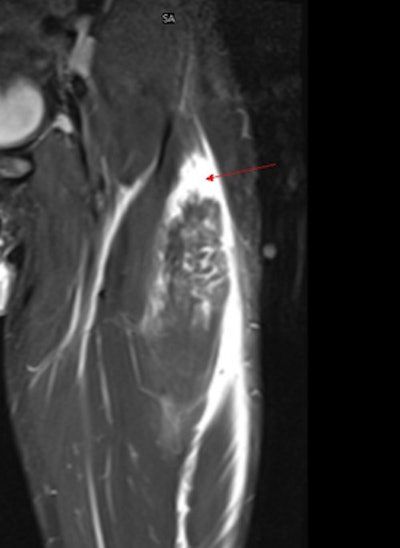

Remote clinical specialists such as musculoskeletal (MSK) and neuroradiologists can then quickly review the images and, if needed, send an embedded annotated image -- saved and indexed alongside the original scan, together with their online report. For the player, the club, and the club doctor, the key advantage is rapid access to specialist sports medical opinion. In addition, the system allows clubs to create a comprehensive club archive of all their diagnostic images that can be sent online from the imaging centers or imported from CDs.

Other uses of the network include supporting the UEFA Champions League's research program into the relationship between hamstring injury severity and return to play times for footballers. A European network is also currently under development to provide image and report communications to support the Team Sky medical team.